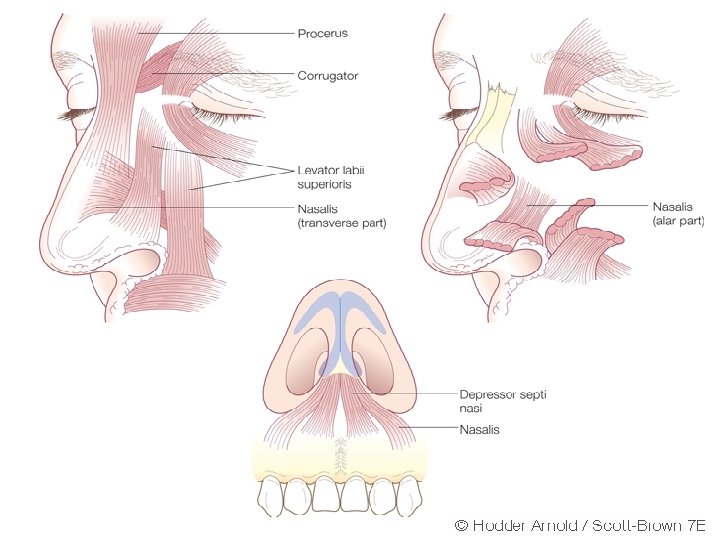

• • • Nasal musculature: a) Procerus b) Nasalis (transverse and alar part) c) Levator labi superioris alaque nasi d) Anterior and posterior dialator naris e) Depressor septi